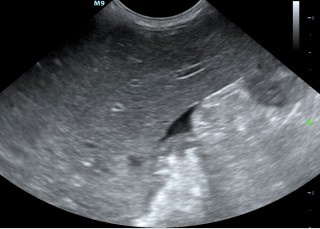

Echografie buik

Met een echo onderzoek kunnen we goed de organen bekijken. We bekijken en beoordelen het orgaan naar grootte, vorm en inhoud. Je kunt alle organen goed onderzoeken. Voor het beoordelen van de maag is het belangrijk dat het dier nuchter komt. Om de wand van de urineblaas goed te kunnen beoordelen moet de blaas gevuld zijn.

De organen die we routinematig beoordelen zijn:

Blaas - Prostaat - Baarmoeder/eierstokken - Lymfeklieren - Darmen - Nieren - Bijnieren - Milt - Alvleesklier - Maag - Lever

De buik in beeld

Hieronder zie je een aantal foto's van de buik met achtereenvolgens; blaasontsteking, blaastumor, vroege dracht hond 19 dagen, vergrote eierstok, lever, nier.